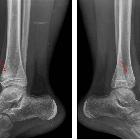

Plain radiograph

Initially to examine the symptomatic site:

- early stages: osteolytic lesion

- later stages: progressive sclerosis

Lesions can range between purely osteolytic, osteolytic with a sclerotic rim, mixed lytic and sclerotic, and purely sclerotic.